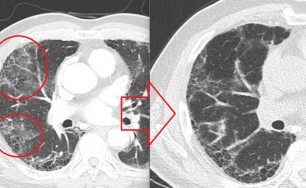

기관지확장증의 CT 사진

​기관지벽의 근육 및 탄력 성분의 파괴로 인해 기관지가 비정상적으로 늘어나 여러가지 문제를 일으키는 질환을 말합니다.

확장된 기관지 내부에는 가래가 고이게 되는데 기관지가 손상되어 있는 상황이므로 잘 빠져나가지 못하게 되고 이로 인해 쉽게 감염되고 그러면서 기관지 벽이 약해집니다. 이렇게 되면 기관지가 쉽게 파괴되고 다시 가래가 증가되는 악순환이 형성됩니다.